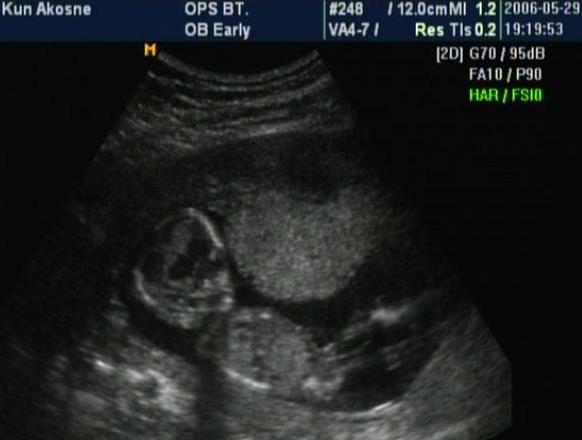

Hát örömmel jelentem, hogy meg volt a 12+3 napon az UH vizsgálatom. ÉS mindent rendben találtak!!!! :D

A CRL 67mm, a BDP 22mm, a tarkóredő 1,6 és van orrcsontja is.

Elvileg aznap este még megyünk 4D-s ultrahangra is, feltéve ha odaérünk. A pármon szeretne elmenni mindenáron, és akkor megbeszéltük, hogy most meg a terhesség vége felé elmegyünk még egyszer aztán ennyi.

Hétfőn elmentem a Védőnőhöz (Pocsai Jánosné), aki nagyon aranyos, csak egy kicst lassúnak tűnt, főleg annak a fényében, hogy 6-tól rendel én már 1/2 6-ra ott voltam, hogy biztosan első legyek. Egy órát voltam nála, amíg felvette az adataimat, végülis semmi más nem történt. Viszont 1/4 nyolcra volt a rendelés a 4d uh-n.Mivel a párom mindenképpen szerette volna látni. Ja és az igaz, hogy nem olyan élvehető a kép, mert pl. Az ujjacsáit nem láttam tisztán, de az lehet, hogy a könnytől volt. Viszont az, hogy egyfolytában mozgott, ugy kapott a kezecskéjével a levegőben, mint a kismacska szokott a lógó madzagdarab után. A szája egyfolytában járt, kinyitotta összecsukta. Szerintünk még mosolygott is.MEg olyan kirdásokat végzett a lábaival, hogy ha nagykorában is ezt csinálja, nekem ki fog lyukadni az oldalam. :)

Nem tudom, hogy minden kismagzat ilyen virgonc-e ebben a korban, de ő ugrált, a fenekét mutatta, stb. Ja és az tetszett a legjobban, hogy hátravetette többszür is magát, mint egy kisbaba. :)